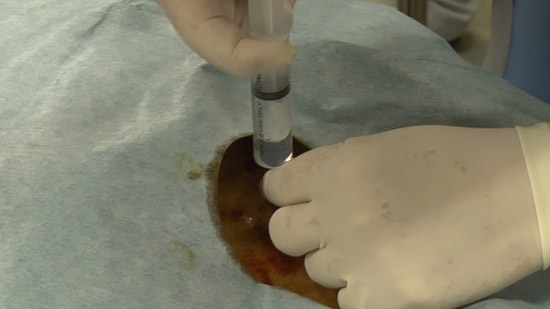

(2)Set the positioning by checking the puncture site along with the image on the radiological screen.

(4)Conduct an epidural puncture by the resistance loss method, checking with the image on the radioscopy screen.

※Inject the contrast medium and check it again. Capture a confirmation image at the same time.